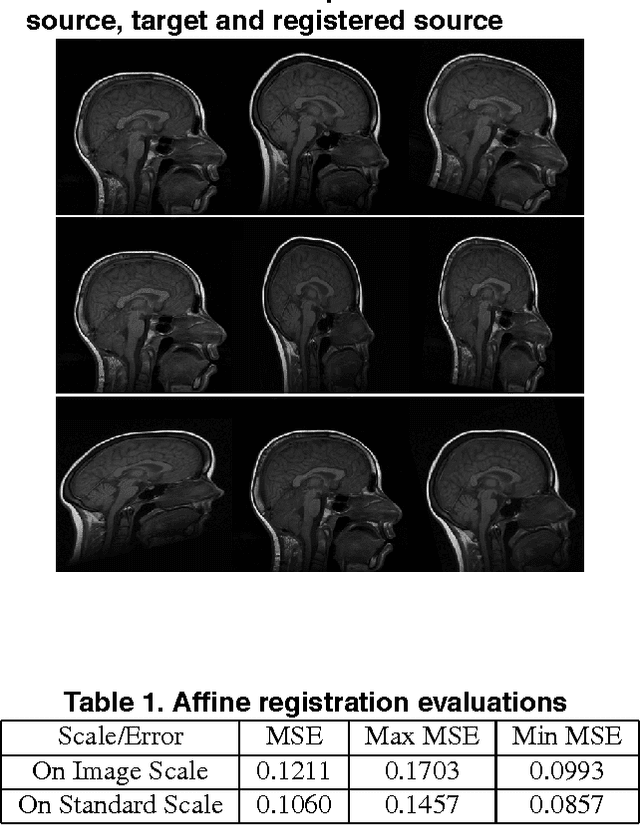

Medical image registration is a difficult problem. Not only a registration algorithm needs to capture both large and small scale image deformations, it also has to deal with global and local image intensity variations. In this paper we describe a new multiresolution elastic image registration method that challenges these difficulties in image registration. To capture large and small scale image deformations, we use both global and local affine transformation algorithms. To address global and local image intensity variations, we apply an image intensity standardization algorithm to correct image intensity variations. This transforms image intensities into a standard intensity scale, which allows highly accurate registration of medical images.